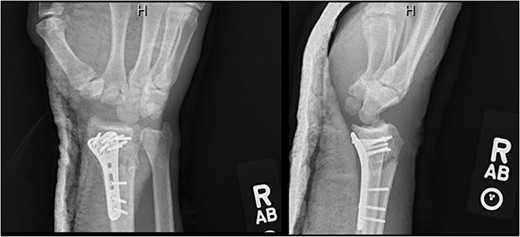

An unhelmeted 59-year-old male presented to the trauma bay at our institution after being involved in a motorcycle accident. This polytraumatized patient had been intubated prior to arrival and evaluation revealed numerous orthopedic injuries, including a right dorsal lunate dislocation (Fig. 1). Other injuries included a left distal femur fracture, left superior and inferior rami fractures, left APC II pelvic ring fracture, left closed tibia/fibula fractures, a Type III open right tibial shaft fracture, a right anterior column acetabulum fracture, and a Type I open right distal radius fracture. Traumatic subarachnoid hemorrhage to the bilateral frontal lobes, a unilateral occipital condyle fracture, a C1 fracture posterior arch fracture, a craniocervical dislocation, and numerous rib fractures were also noted. In addition to splinting all other peripheral injuries, the right distal radius fracture and lunate dislocation were closed reduced using a sugartong splint, with the wrist positioned in slight extension (Fig. 2).

Anteroposterior (AP) and lateral views demonstrating the right distal radius and perilunate dislocation after closed reduction in the trauma bay.